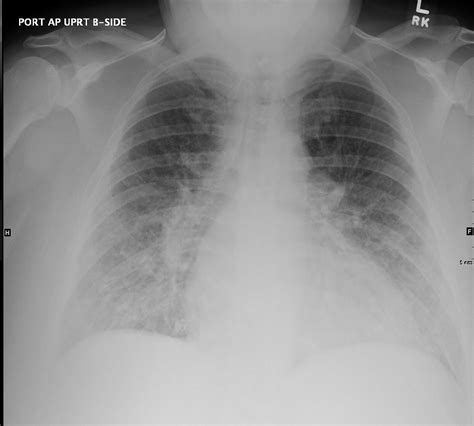

As this fluid tracks into the interlobular septa, it expands these structures. When viewed on a 2D chest X-ray, the summation of this fluid-filled tissue manifests as the classic, short, horizontal lines that clinicians search for. If the pressure continues to rise, the fluid may eventually cross into the alveolar space, leading to frank alveolar pulmonary edema, which presents as patchy, fluffy opacities on imaging.

From a clinical management perspective, the identification of Kerley B lines serves as an important trigger for diagnostic and therapeutic decision-making. If a patient presenting with dyspnea is found to have these lines on a portable chest X-ray, it often justifies the immediate initiation of heart failure therapy, such as intravenous diuretics, pending further diagnostic workup like an echocardiogram or NT-proBNP testing.

It is important to remember that these lines reflect the "interstitial" phase of edema. This is a critical window; recognizing them early allows clinicians to treat the fluid overload before the patient progresses to severe respiratory distress and alveolar flooding, which would necessitate more aggressive intervention, such as non-invasive positive pressure ventilation (NIPPV) or intubation.